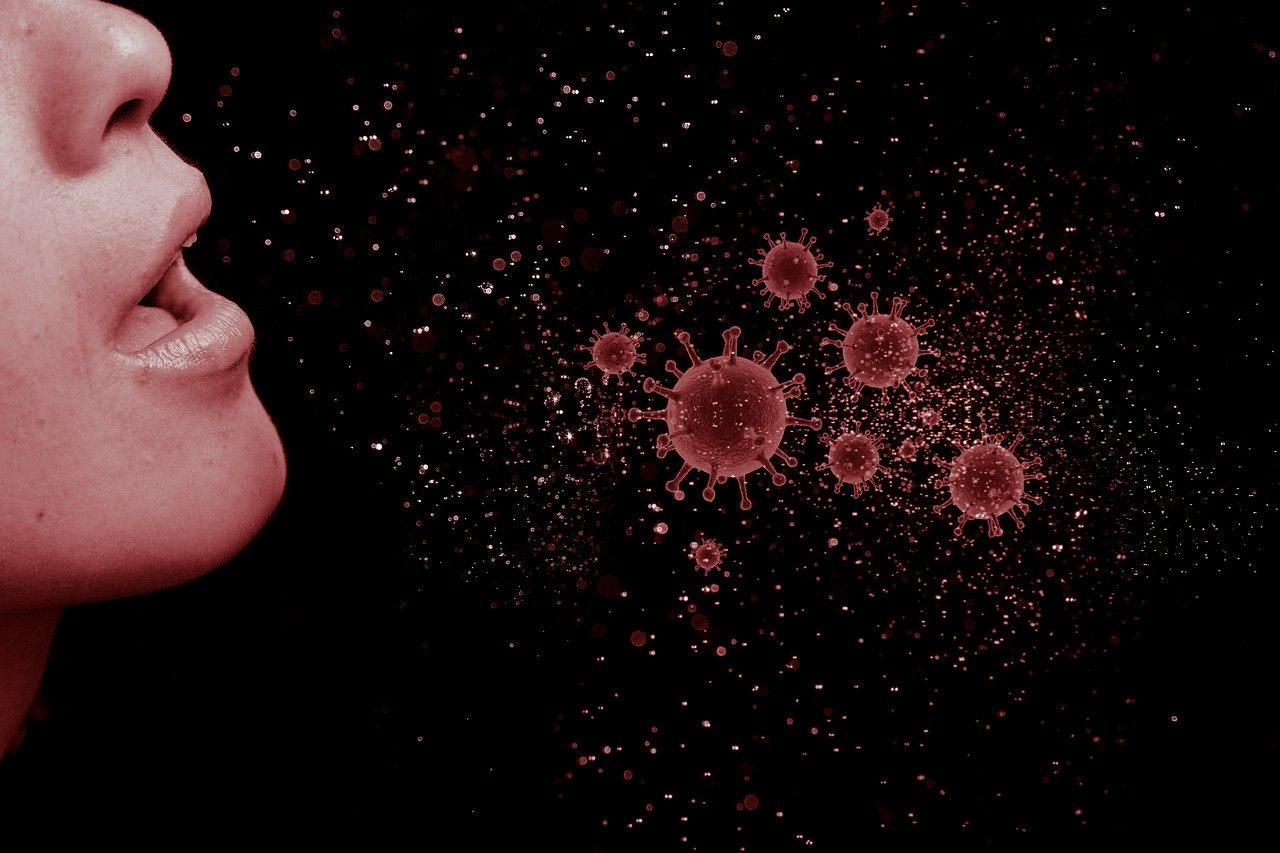

Напомним, ранее ученые установили, что лишь за минуту разговора в воздух выбрасывается по меньшей мере 1000 микрокапель. Некоторые из них держатся на том же месте до 8 минут, а некоторые – до 14.

Кроме того, физики утверждают, что социальная дистанция в 2 метра работает только в том случае, если скорость воздуха нулевая.

Вирусные капельки после кашля могут путешествовать на неожиданное расстояние / AIP